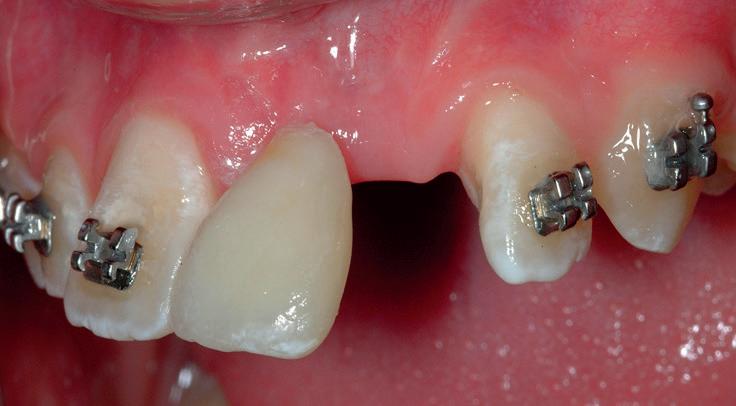

RECONFIGURAREA suportului osos implantar. În cazul prezentat, după ani de terapie ortodontică incorect executată, dezvoltarea dentară a pacientului a complicat obținerea unui zâmbet estetic. S-a reanalizat și s-a optat pentru abordare interdisciplinară care cuprinde chirurgia parodontală, un al doilea tratament

ortodontic și protetica pentru a oferi îngrijirea comprehensivă.